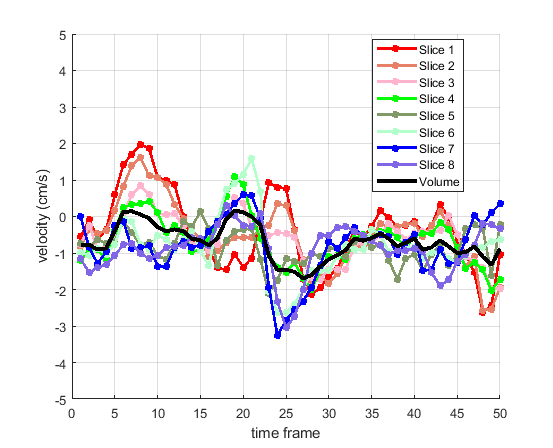

Time courses of the estimated translational component per subject, frame, slice and volume along the 3 velocity directions x, y and z are presented in Fig.6 - Fig.8.